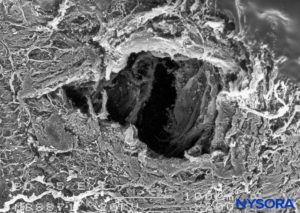

FIGURE 19. Dura-arachnoid lesion produced with 25-G Quincke needle. Arachnoid surface. Scanning electron microscopy. Magnification ×200. (Reproduced with permission from Reina MA, Castedo J, López A. Cefalea pospunción dural: Ultraestructura de las lesiones durales y agujas espinales usadas en las punciones lumbares. Rev Arg Anestesiol. 2008 Jan-Mar 66(1):6-26.)FIGURE 19. Dura-arachnoid lesion produced with 25-G Quincke needle. Arachnoid surface. Scanning electron microscopy. Magnification ×200. (Reproduced with permission from Reina MA, Castedo J, López A. Cefalea pospunción dural: Ultraestructura de las lesiones durales y agujas espinales usadas en las punciones lumbares. Rev Arg Anestesiol. 2008 Jan-Mar 66(1):6-26.)

Piercing the dural sac during a subarachnoid block causes mechanical disruption of both the dura mater and the arachnoid layer. The cross-sectional area of the puncture site produced by a 25-gauge needle is similar regardless of whether the needle has a pencil point or a cutting end. However, the morphology of the lesion varies depending on the design of the needle tip. Pencil-point needles produce a greater and rougher-appearing injury to the dural fibers, while cutting needles produce a U-shaped lesion or flap resembling the open lid of a tin can (Figures 8 to 31).

When using cutting (long bevel) needles, bevel orientation (eg, parallel or perpendicular to the main axis of the cord) does not significantly affect the size or morphology of the lesions in the dura and arachnoid lamina (see Figure 24). The lesion that the needle produces in the dural sac has two components, dural and arachnoid. It is believed that the arachnoid component is vital in limiting cerebrospinal fluid leakage from the subarachnoid space to the epidural space. Therefore, the size and morphology of arachnoid lesions seem to be more important for laminar sealing and cerebrospinal leakage than the size and morphology of dural lacerations.

The incidence of postdural puncture headache (PDPH) has been thought that is affected by the type of needle used (pencil point versus cutting) and of the bevel. The traditional belief that cutting needles result in larger dural lesions (tears) was established in the 1940s and may have been the consequence of the imperfections in the needle design of that era. Modern needles, however, produce clean, U-shaped lesion or flap resembling the open lid of a tin can (see Figure 24).

After needle withdrawal, the U-shaped flap tends to return to its original position due to cerebrospinal fluid pressure and the elastic properties of the dura mater. The dural orifice is almost completely occluded after approximately 15 minutes. On the other hand, lesions produced by pencil-point needles involve a more complex lesion with fiber tearing, sectioning, and separation. The extent of the dural lesion caused by a needle depends on several factors, including the external diameter of the needle, dural and arachnoid sealing mechanisms, needle-tip design, and the quality of needle manufacturing. Needles having the same tip design but different manufacturing methods may not have the same surface quality and may contain microfractures or imperfections, resulting in more or less extensive dural fiber tearing and residual lesions.